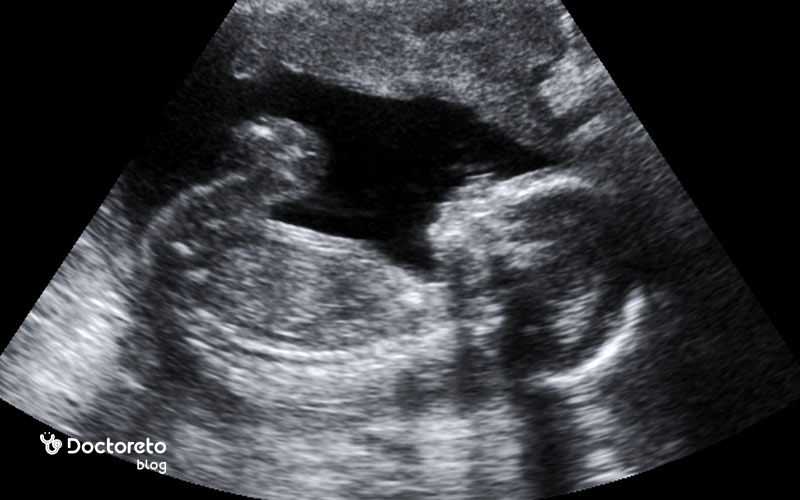

سونوگرافی در هفته هفدهم بارداری

در هفته هفدهم بارداری، سونوگرافی برای ارزیابی رشد و سلامت جنین اهمیت زیادی دارد. در این مرحله، پزشک اندازه جنین، ضربان قلب، حرکات، محل جفت و میزان مایع آمنیوتیک را بررسی میکند و میتواند شکلگیری اندامهایی مانند مغز، قلب، کلیهها و استخوانها را مشاهده کند. در بیشتر موارد، جنسیت جنین نیز قابل تشخیص است، هرچند ممکن است به وضعیت قرارگیری او بستگی داشته باشد. این سونوگرافی به پزشک کمک میکند تا از رشد طبیعی جنین اطمینان حاصل کرده و در صورت نیاز، زمان دقیق انجام سونوگرافی آنومالیها را برای هفتههای ۱۸ تا ۲۰ تعیین کند.